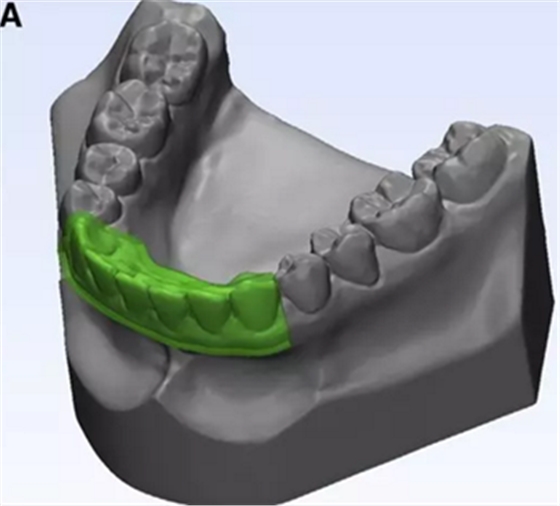

在CBCT成像之前,使用物理下頜石膏模型制造牙合板(圖3中的A)。原始2毫米厚的透明薄板在下頜骨模型上熱成形。然后修剪薄板以覆蓋下頜前牙區(qū),起自牙齦邊緣而終止于雙側(cè)尖牙的遠中面(圖3,B)。

圖3. A,熱成型薄板的3D模型; B,薄板口內(nèi)試戴。